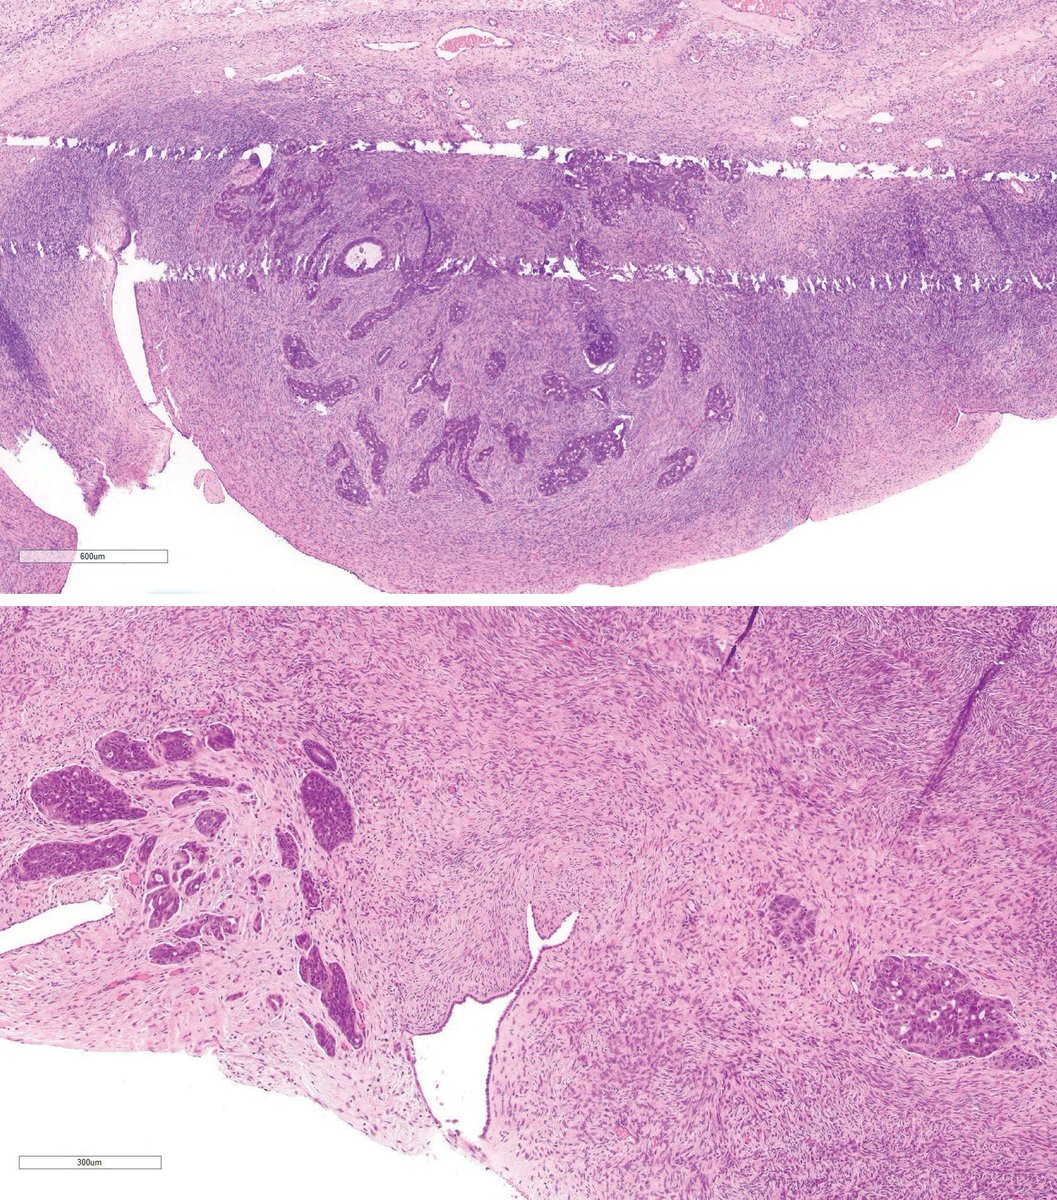

🚨SEMINOMA #gupath - sheets of cells separated by fibrous bands - cells in center furthest from vascular supply➡️dark cytoplasm + necrosis; mimic embryonal CA - discohesive cells➡️mimic EC/YST; still display seminoma cytology - keratin #IHC➡️para-nuclear labeling=still seminoma

🚨SEMINOMA #gupath

- sheets of cells separated by fibrous bands

- cells in center furthest from vascular supply➡️dark cytoplasm + necrosis; mimic embryonal CA

- discohesive cells➡️mimic EC/YST; still display seminoma cytology

- keratin #IHC➡️para-nuclear labeling=still seminoma